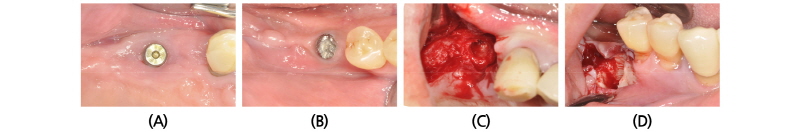

4달 뒤, 내원하였을 때 수술 부위에 특별한 이상 소견 관찰되지 않았다(Fig. 4A). 국소마취하에 판막을 거상하고(Fig. 4B), titanium mesh를 제거하였다(Fig. 4C). #15, #17 부위에 임플란트를 식립하였고(Fig. 4D), apically positioned flap으로 봉합하였다(Fig. 4E). 2달 뒤 체크하러 왔을 때 큰 이상소견 보이지 않았고(Fig. 4F), 임플란트 식립 4개월 후에 최종 보철 시행하였다(Fig. 5).